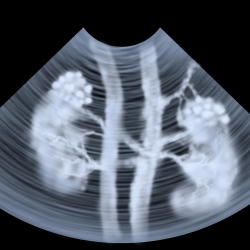

Kidney ultrasound or imaging